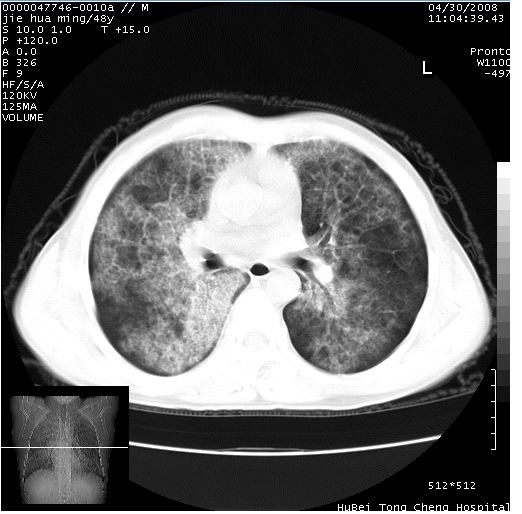

以下是引用dr.yang在2008-5-1 6:25:00的发言:[br]两肺广泛毛玻璃样的片状影,密度不均,边缘欠清,呈碎石路样改变,[br]考虑,1双肺间质性肺炎,2肺泡蛋白沉积症3支气管肺泡癌[br]

以下是引用hhcckk在2008-5-1 8:06:00的发言:[br]支持肺泡蛋白沉积症[br]依据:[br]1、病灶边缘清楚----地图征[br]2、病灶内部小叶间隔或小叶内间隔增厚所形成的网格状影----碎石路样表现[br]3、抗炎治疗无效(炎症抗炎治疗有效)[br]4、纵隔内未见肿大淋巴结(肺泡细胞癌时常有)[br][br]附肺泡蛋白沉积症资料[br][br]肺泡蛋白沉积症(pulmonary alveolar proteinosis)是一种原因不明的以肺泡腔内大量含脂糖蛋白样物质沉积为特征的疾病。[br]病理改变:(1)肺泡和细支气管腔内充满大量含脂糖蛋白样的粘稠物质,该物质为颗粒状或絮状的糖原pas染色阳性的磷脂蛋白。(2)肺泡壁及其间隔无异常改变。胸膜和淋巴结不受累及。(3)晚期可出现弥漫性肺间质纤维化。[br]临床表现:(1)好发年龄30~50岁,男性多于女性,偶见于儿童;(2)主要症状为呼吸困难、咳嗽、低热、消瘦、低氧血症和杵状指等。1/3的患者无症状。(3)实验室检查:痰液或肺泡灌洗液中可找到pas染色阳性颗粒物质。[br]hrct表现:肺泡蛋白沉积症具有特征性改变,即“碎石路样”表现(crazy-paving appearance,cpa)。主要包括(1)斑片状磨玻璃影:指肺野密度朦胧增加,内可见肺血管纹理影,系肺泡腔内充满低密度的磷脂蛋白物质所致。(2)其内部小叶间隔或小叶内间隔增厚所形成的网格状影,为小叶间隔水肿、肺泡壁内淋巴细胞和巨噬细胞浸润以及小叶内淋巴管扩张的缘故。(3)病灶边缘清楚,呈地图样分布于肺野外围或肺门及中央区。[br]

以下是引用zsl6918在2008-5-1 7:35:00的发言:[br]双肺磨玻璃样病变,可见铺碎路石征,病变区与正常区交错。边界清晰。符合肺泡蛋白质沉着征,高分辨扫描会更清楚漂亮。建议临床肺泡灌洗。

以下是引用yangyudong333在2008-5-1 5:36:00的发言:[br][br] 两肺广泛毛玻璃样的片状影,密度不均,边缘欠清,呈碎石路样改变,[br]考虑,1双肺间质性肺炎,2肺泡蛋白沉积症[br]